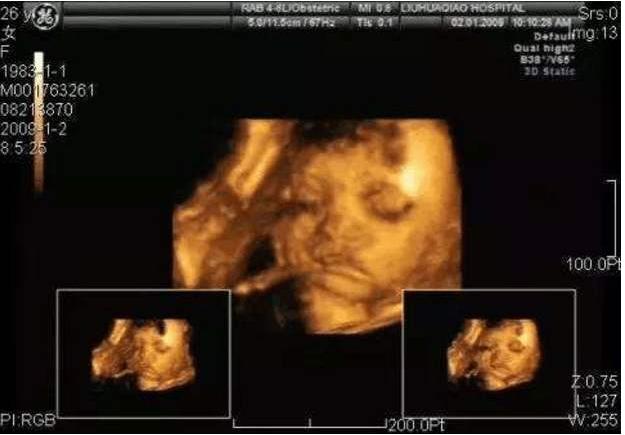

四维超声则是在三维彩超的基础上增加了时间维度,通过三维容积探头连续采集图像,同时进行同步立体图像的数据处理,获得实时动态的胎儿的立体结构图像,能实时捕捉到胎儿的运动,可有效筛查胎儿畸形。

当然,很多医院也为了迎合孕妈妈的心理,大家都想知道胎儿的长相,留下一张胎儿的纪念照片,所以好多医院所宣传的四维彩超,其实只是将胎儿系统彩超检查中的一个三维图像打印出来而已,也就变成了大家所说的胎儿四维彩超了。

目前,多数医院都会在孕期安排2次进行系统畸形筛查的四维彩超,第一次在22周左右比较好,第二次在32周左右比较好。